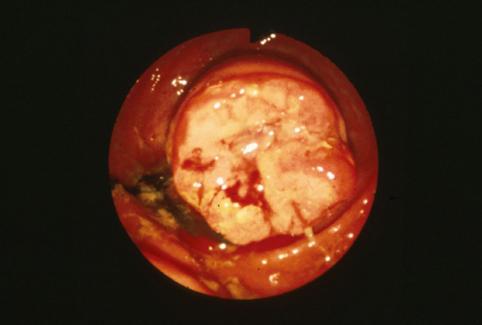

Criteria of Hist.ClassificationMalignant epithelial tumor/Adenocarcinoma

LocationLarge intestine(Colon)/Appendix

Technique, MethodEndoscopy

Macroscopic TypesType 2 Ulcerated type with clear margin/

Size25 - 29

Depth of Tumor Invasionserosa (adventitia)